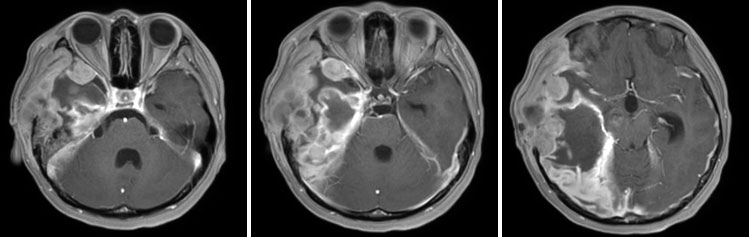

术后短期内(3周)迅速复发

经过放疗+药物治疗后2月余肿瘤缓解